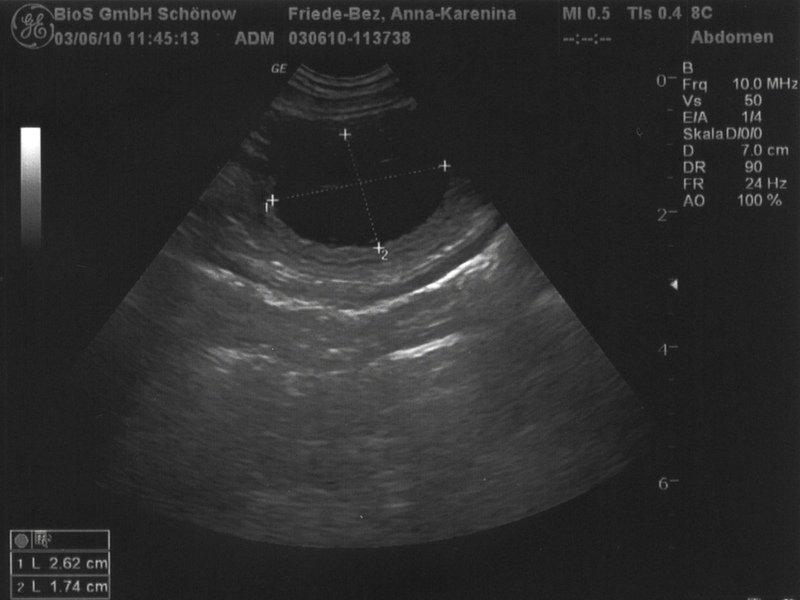

Ultraschall Anna Karenina 3.6.2010

Das Ultraschallbild heute früh hat Gewißheit gebracht, daß Anna Karenina trächtig ist. Drei Fruchtblasen (im Bild als schwarze Ovale zu sehen, einmal ist auch die Größe gemessen) waren zu erkennen. Das heißt aber nicht, daß nur drei Welpen zu erwarten sind. Es können auch durchaus doppelt so viele werden.